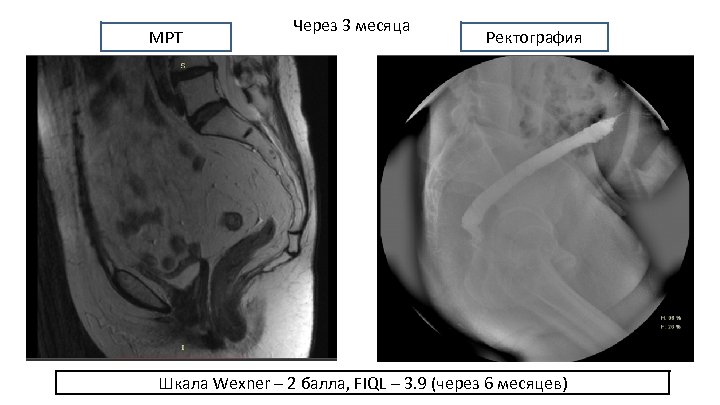

МРТ Через 3 месяца Ректография Шкала Wexner – 2 балла, FIQL – 3. 9 (через 6 месяцев)